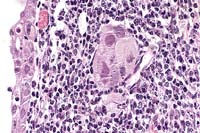

Contributor's Diagnosis and Comments: Lipogranulomatous lymphangitis and lymphangiectasia, multifocal, chronic, moderately severe, small intestine and mesenteric lymphatics.

Lymphatic structures within the small intestine villi, lamina propria, and muscular tunics are markedly dilated. Dilated lymphatic spaces in muscular tunics frequently contain accumulations of large macrophages. The dilated lacteals result in multifocal marked distortion of mucosal villi and expansion of the lamina propria. There is mild lymphocytic and plasmacytic infiltration throughout the lamina propria and focal elongation of crypts. Mesenteric lymphatics are also dilated. Associated mesenteric adipose connective tissue contains areas of fat necrosis, proliferation of fibroblasts, and accumulations of macrophages, neutrophils and hyperchromatic debris. Special stains for fungal and bacterial organisms were negative.

The lesions in this case are consistent with those described for lipogranulomatous lymphangiectasia, a rare condition that has been described in humans, cattle, and dogs. The pathogenesis of lipogranulomatous lymphangiectasis is poorly understood. It has been associated with some cases of intestinal lymphangiectasia. It has not been determined whether stasis of lymph precedes inflammation or if an initial inflammatory reaction impedes lymph flow. Lipogranulomas have been seen following trauma in an acquired form of lymphangiectasia. It also seems likely that initial lymph stasis and secondary lymphatic leakage can result in subsequent inflammation and granuloma formation, as suggested by some researchers.

Case 18-3. Intestine. Engorged lymphatics have a narrow rim of small lymphocytes and are expanding the villi. 10X

AFIP Diagnosis: Small intestine: Lymphangiectasia, transmural, diffuse, moderate, with multifocal lipogranulomatous lymphangitis and perilymphangitis, Pug, canine.

Conference Note: Lymphangiectasia is a common cause of malabsorption and protein-losing enteropathy in dogs. The cause is often presumed to be lymphatic obstruction, such as by neoplastic or inflammatory processes in mesenteric lymph nodes. In many cases, the cause cannot be determined. As the contributor noted, lipogranulomatous inflammation of lymphatics is not common, and the cause is obscure.

Clinical signs of lymphangiectasia result from malabsorption of long-chain fatty acids and loss of plasma proteins and lymph into the gut. Signs include chronic diarrhea, wasting, hypoproteinemia, lymphopenia, relative hypocalcemia, and hypocholesterolemia. Hypoalbuminemia results in peripheral edema, ascites, and hydrothorax, and may have thereby contributed to this dog's chronic cough.